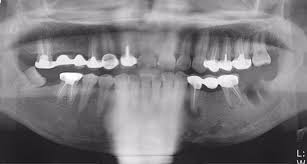

| 치주염 | 잇몸이 내려앉고 치아 흔들림 | 치주치료, 잇몸수술 |